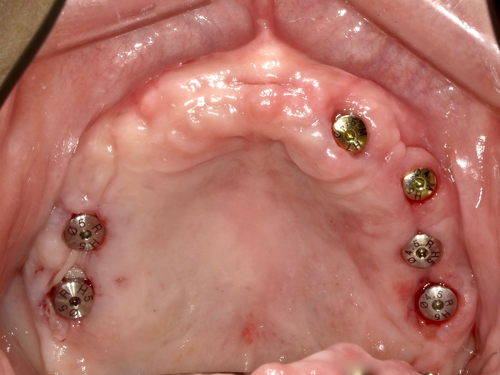

CT画像の分析を徹底的にした結果、僅かに残された骨の厚みと高さのある部分に、6本のインプラントを移植することが出来ました。

長時間の施術、お疲れさまでした。アゴの骨幅が薄く、高さも無い場所に、歯肉をメスで切らずにインプラントを移植するのは相当ハードでしたが、僅かに骨のありそうな場所にインプラント移植を行いました。総て骨とガッチリ固定してくれることを願っています。また、スタッフのみんなも一年間本当にありがとう!